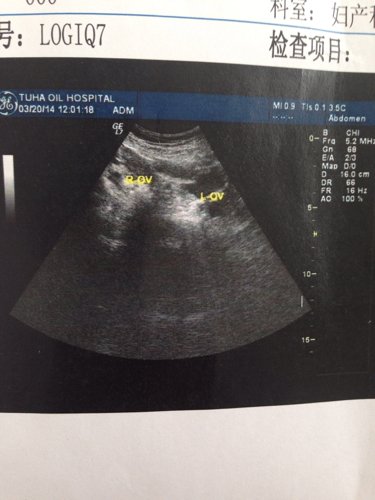

子宫前位,大小约58x49x32mm,形态饱满,肌层回声均匀,宫腔内见16x13x8mm的厚壁双环

子宫前位,大小约58x49x32mm,形态饱满,肌层回声均匀,宫腔内见16x13x8mm的厚壁双环囊状回声,未见胚芽及原始心管搏动,孕囊周边可见10X6mm无回声,宫颈前后26mm,内未见明显占位。子宫肠窝可见34x10mm的无回声。我想问我怀孕多长时间

病情分析: 你的情况考虑根据孕囊情况,考虑怀孕应该在34天左右的情况,注意休息的 指导意见: 考虑检查结果伴随积液的情况预防先兆流产的可能,建议定期到医院检查胎儿的情况较大,同时建议应该用药复查多喝水